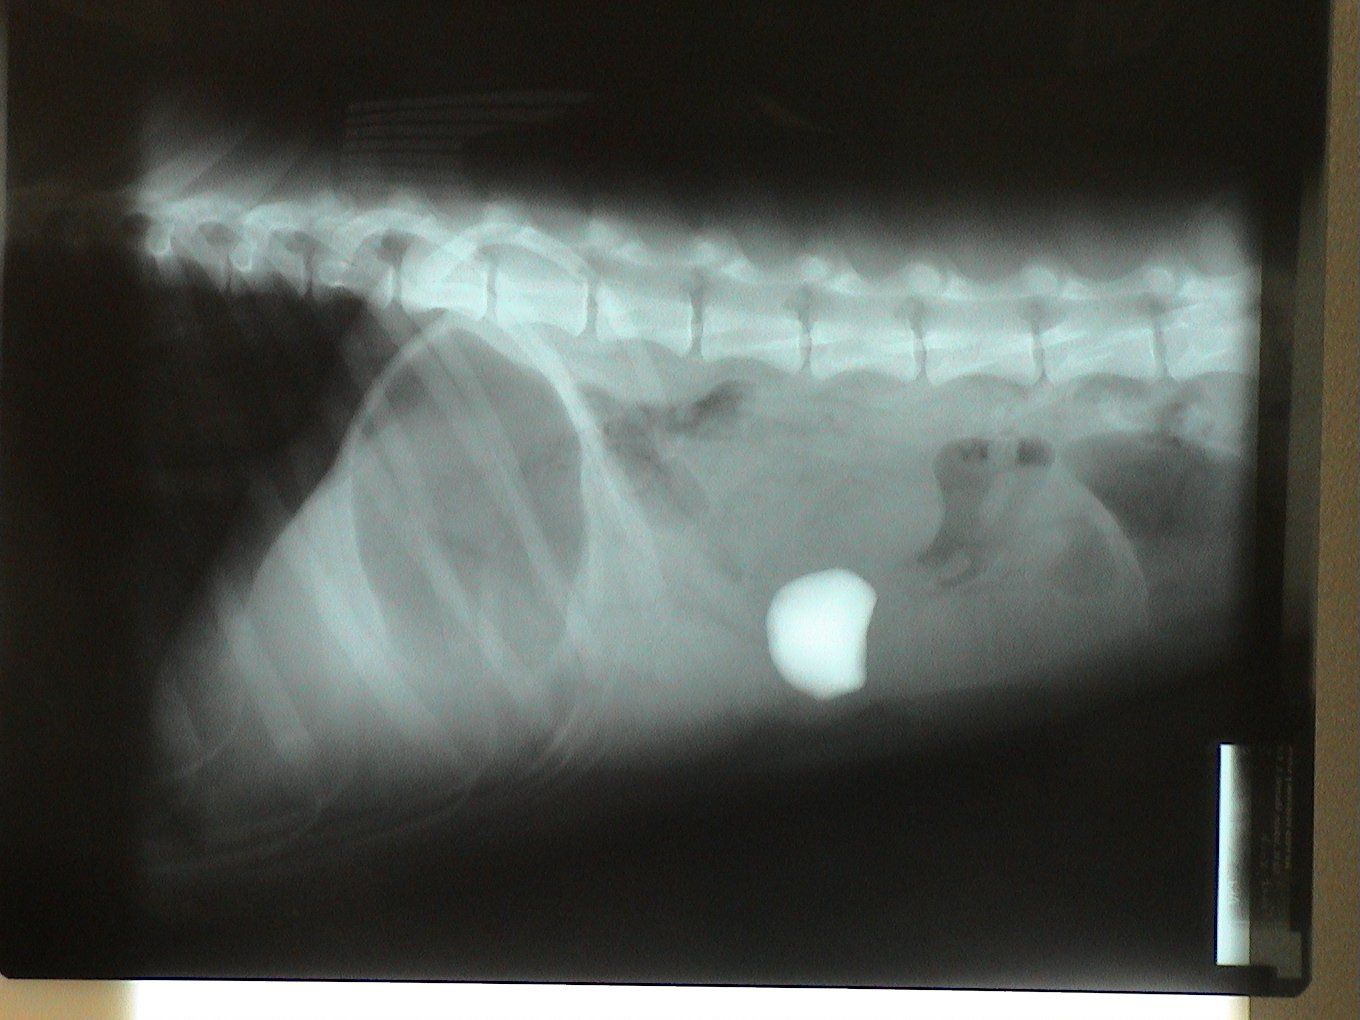

Radiographs (x-rays) were taken and his problem became very obvious! A previously ingested rock had become lodged in the small intestine causing an obstruction.

Green circle: Gas filled stomach. Secondary to vomiting, the stomach can become distended with gas. Red circle: Rock in small intestine. Yellow circle: Gas in colon. Secondary to an obstruction, gas can accumulate in the bowel.

Two sets of radiographs are always taken to localize lesions and identify problems. Radiographs are flat pictures of three-dimensional animals! If one view is taken, things can be lost as structures will overlap each other. For example, the rock is located on the left side of the abdomen which is clearly evident on the second set of radiographs. This is not evident in the first set since the left and right sides of the dog overlap each other.

Notice the difference in the shape of the circled structures depending on the position of the animal.